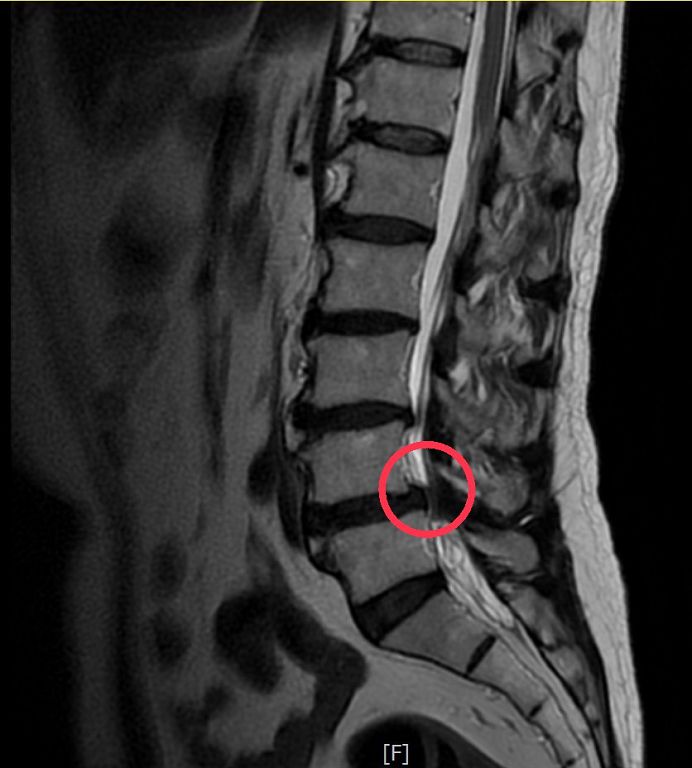

磁振造影顯示黃先生腰椎滑脫,神經受到壓迫。

洪祥益主任表示,經由腰椎X光及核磁共振造影檢查,發現黃先生第4、5節腰椎滑脫及嚴重壓迫神經,同時椎間盤突出,評估後建議以腰椎微創融合手術治療。微創融合手術可以保留肌肉,利用撐開器順著肌肉紋理建立手術路徑,減少組織破壞,不僅傷口小、術後疼痛感低,有助於加速恢復;傳統手術需將背部肌肉剝離,傷口較大、術後恢復較慢,且容易導致核心肌群肌肉萎縮纖維化、僵硬痠痛的後遺症。